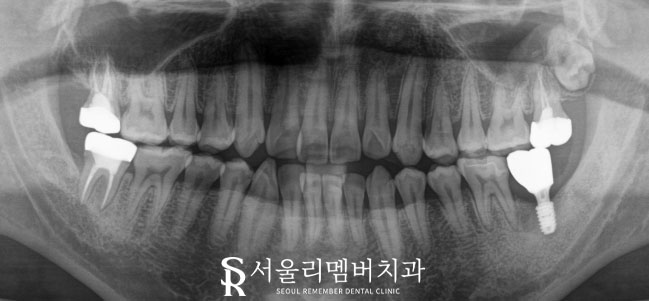

위 사진은 모든 과정을 지나쳐

최종 진료를 마무리한 후의

엑스레이 사진입니다.

디지털 장비들을 이용해서

올바른 위치에 적절하게 식립되었고,

근관 제거 또한 깔끔하게 진행되었네요.